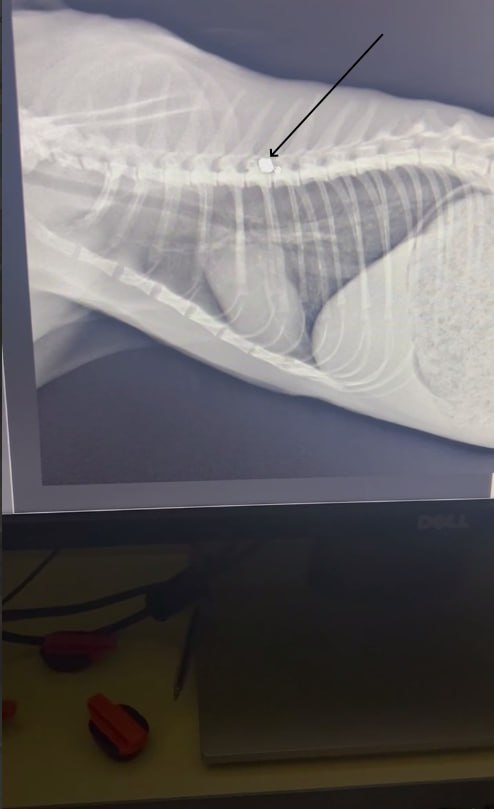

Назначили операцию на 4 мая, врач нашёл входное пулевое отверстие, ему примерно неделя. Пуля давит на позвонки и является источником инфекции. Моча наконец стала светлой, что хорошо.

В ветклинику подбросили кота в ужасном состоянии, был сильный удар. Писает кровью, ветеринары борются за животное как могут. В теле найдены пули.

Мефодий уже в клинике в ожидании операции, УЗИ сердца сделали, без патологий, анестезиолог провел консультацию, теперь ждём новостей из клиники, после операции должны позвонить.